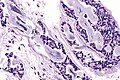

Adenoid cystic carcinoma. H&E stain. | |

| LM | cribriform architecture (other patterns: solid, cords, (bilayered) tubules), cystic spaces filled with basophilic material, scant cytoplasm in most cells, nucleus - small, hyaline stroma |

- Cribriform architecture or pseudoglandular spaces (classic pattern) - important feature.

- Other patterns: solid, cords, (bilayered) tubules.

- Cystic spaces filled with basophilic material (that is PAS +ve) - key feature.

- Scant cytoplasm in most cells (myoepithelial cells) - clear/eosinophilic.

- Moderate eosinophilic cytoplasm in the (rare) ductal cells.

- Nucleus - small.

- May be angulated (carrot-shaped) - myoepithelial cells; round/ovoid in ductal cells.

- Hyaline stroma.

The sections show a tumour with a cribriform architecture. The cystic spaces have basophilic material. The tumour cells are carrot-like and have scant/modest cytoplasm.